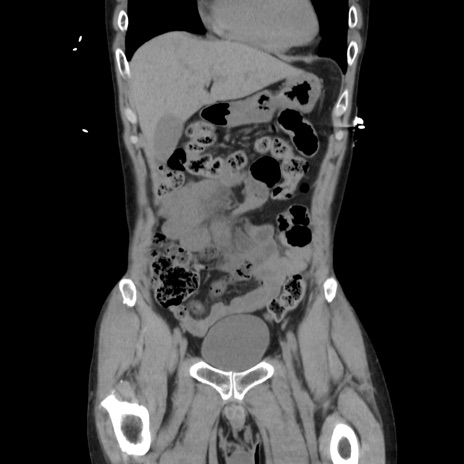

症例37(冠状断像)

【症例】40歳代 男性

【主訴】腹痛

【現病歴】4時間ほど前に電車に乗車中に臍部上より腹痛出現。徐々に増悪し起立困難となり、救急外来受診。生ものは数日食べていない。今朝お雑煮を食べた。

【身体所見】BT 36.8℃、BP 117/84mmHg、HR 91/min、SpO2 97%、苦悶様、腹部:臍上部広範囲圧痛あり、反跳痛±

【データ】WBC 8100、CRP 0.03